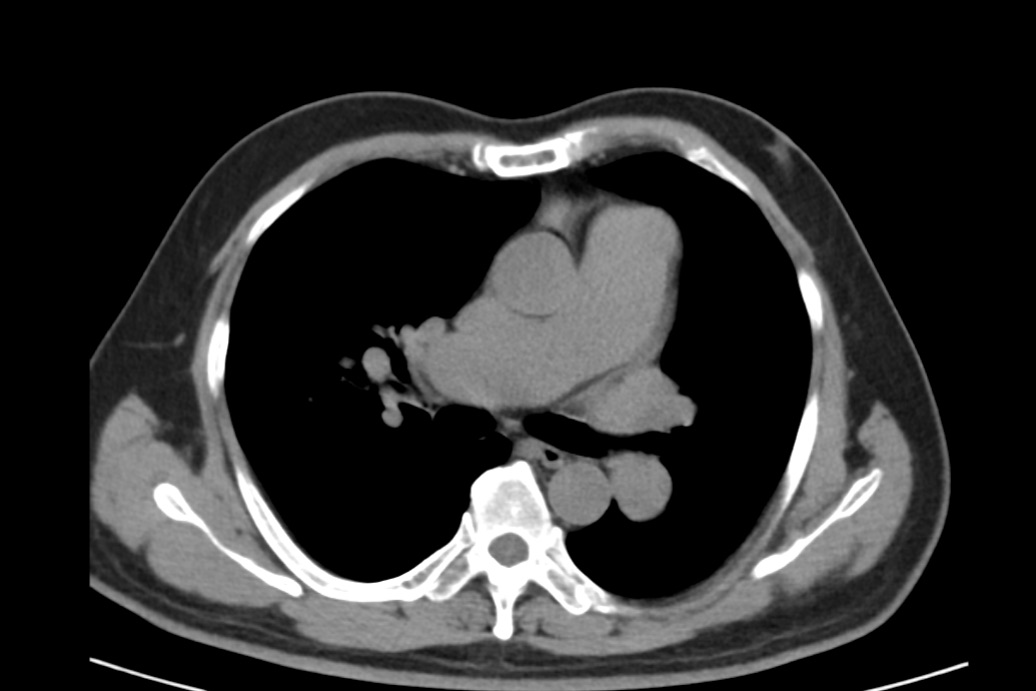

患者65岁,定期体检,自觉身体健康状况良好,既往无心脏疾病史。本次因前列腺疾病入院,在完善术前检查时,胸部CT却显示心脏明显增大,肺动脉及其分支明显增粗,提示肺动脉高压可能。这个异常信息立即引起了主管麻醉医生黄焜的关注,于是安排患者进行了心脏彩超检查。心脏彩超显示:房间隔中份回声失落27*23mm,房间隔缺损(继发孔型)房水平左向右分流,左室收缩功能测值正常。

图:CT提示肺动脉及其分枝明显增粗